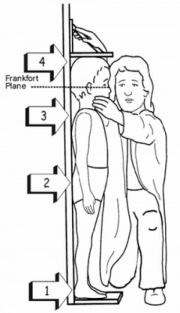

| 05:46, 19 באוגוסט 2014 | מדידת גובה.png (קובץ) |  |

111 קילו־בייטים | Motyk | 1 | |